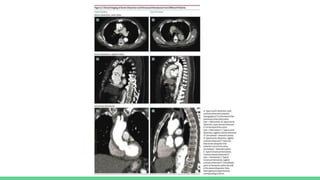

● CT is the imaging modality of choice for diagnostic of dissection

● CT protocols should be both with or without IV contrast

● CT may also diagnose intramural hematoma and penetrating atherosclerotic

ulcer

COMPUTER TOMOGRAPHY

Aortography- The gold standard diagnostic modality for aortic dissection

Benefits includes accurate visualization of the true and false lumen , intimal flap,

● Coronary/Pulmonary/Aortic CT angiography or the triple rule out

which is used to differentiate acute coronary artery disease, pulmonary

embolism and acute aortic dissection has not been shown to improve diagnostic

yield .

● MRI has been used to evaluate stable patients with suspected aortic disease